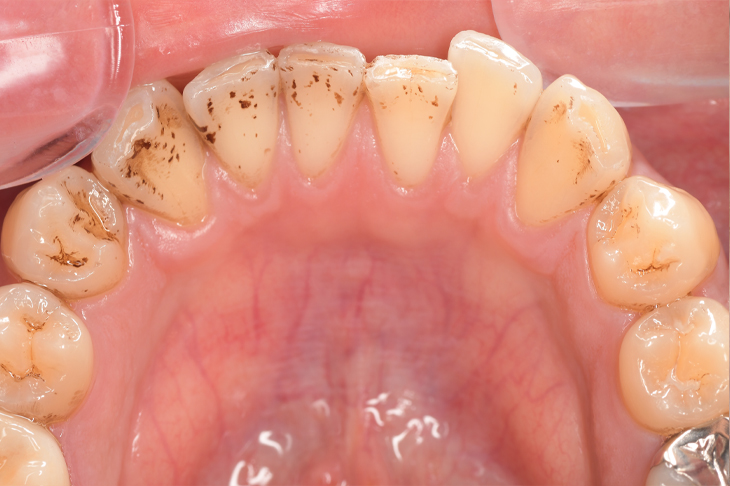

CASE 13

Before

After

| 年齢・性別 | 31歳・男性 |

|---|---|

| 主訴 | 歯石をとりたい |

| 治療内容 | スケーリング |

| 治療期間 | 30分 |

| 治療費 | 1,500円(保険診療) |

| リスク・副作用 | 知覚過敏、歯肉退縮 |

| 治療方針 |

定期的なメインテナンスで歯石を除去していきます。 歯石が付くのを予防するため普段から歯間ブラシ、フロスを活用してセルフケアを行ってもらいます。 |